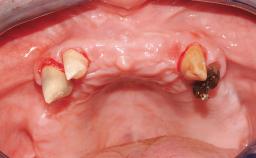

A fully edentulous 65-year-old woman was referred to our clinic for esthetic and functional dental rehabilitation. The patient presented with inadequate complete maxillary and mandibular prostheses, insufficient vertical dimension, and extensive tooth wear. The clinical examination and anamnesis showed no local or systemic contraindications, no signs or symptoms of bruxism, and an absence of smoking habits. The treatment proposed was implant placement in the mandibular interforaminal area and immediate loading with a fixed definitive prosthesis. A removable mucosa-supported complete prosthesis was indicated for the upper jaw, since its bone structure offered satisfactory retention and the financial condition of the patient disfavored a full-mouth implant-supported rehabilitation.

Case Type Edentulous Mandible

Jaw Mandible

Area Full-Arch

# of Teeth All

# of Implants 4